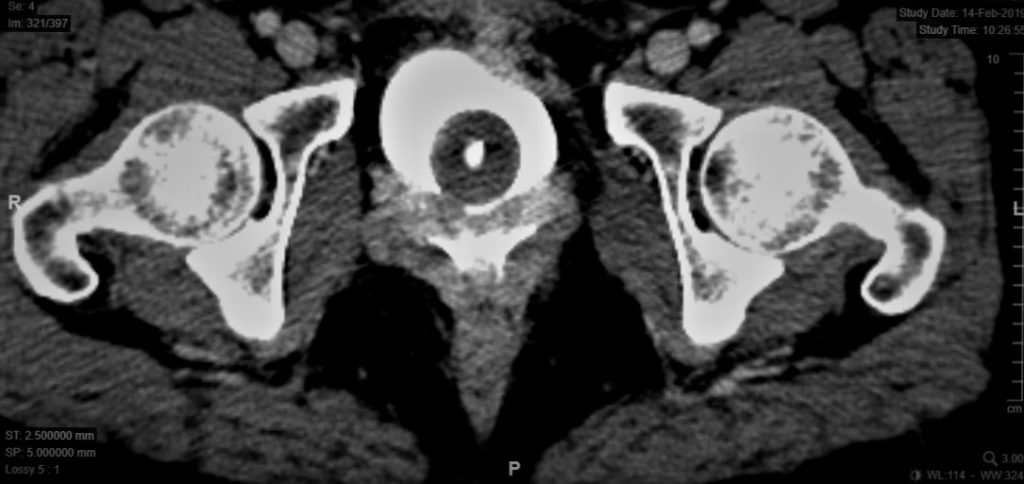

El estudio contrastado de la vía urinaria superior permite reconocer una posible fistula urétero vaginal, que se presenta hasta en un 10% de las pacientes con FVV.53 La cistografía de llenado y la tomografía computada (TAC) permiten objetivar el diagnostico al visualizar la extravasación de medio de contraste desde la vejiga a la vagina. Si se utiliza TAC, otros posibles hallazgos son aire o liquido en la vagina. También permite evaluar las condiciones de la vejiga para planear una resolución quirúrgica (Figura 20). Cuando hay sospecha de compromiso tumoral y/o fístulas complejas, la resonancia de pelvis contrastada puede ser de gran ayuda en la planificación quirúrgica y anticipación de las posibles complicaciones.